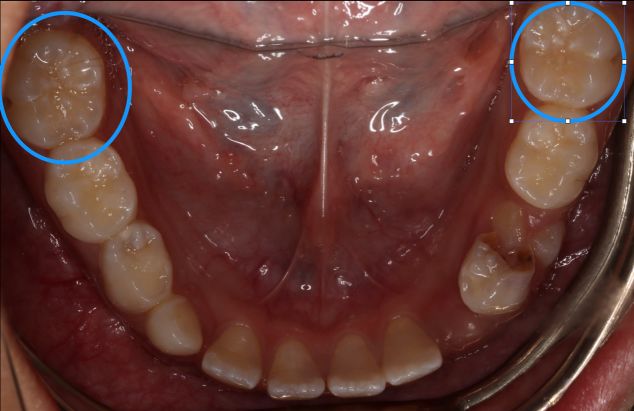

圆圈所示为第一恒磨牙(六龄齿)

现窝沟封闭主要针对的是六龄齿,“六龄齿”(第一恒磨牙)是口腔内最早萌出的恒磨牙,大概在6岁左右萌出,它的咀嚼功能是最强的,由于其自身结构存在许多点隙窝沟,咬合面凹凸不平,难于清洁,易残留食物残渣,并且刷牙也无法将其清除,久而久之,窝沟部位就容易发生龋齿,称为“窝沟龋(qǔ)”。